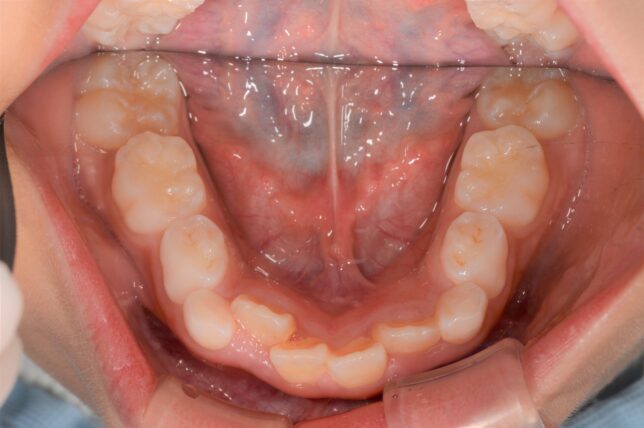

普通の咬み合わせの例↓

治療後↓ 前歯の咬み合わせが、本来の咬み合わせになりました。